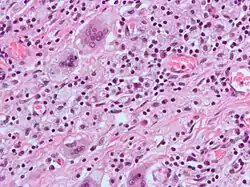

A giant cell (also known as a multinucleated giant cell, or multinucleate giant cell) is a mass formed by the union of several distinct cells (usually histiocytes), often forming a granuloma.[1]

Non-osteoclast MGCs can arise in response to an infection, such as tuberculosis, herpes, or HIV, or as part of a foreign body reaction. These MGCs are cells of monocyte or macrophage lineage fused together. Similar to their monocyte precursors, they can phagocytose foreign materials. However, their large size and extensive membrane ruffling make them better equipped to clear up larger particles. They utilize activated CR3s to ingest complement-opsonized targets. Non-osteoclast MGCs are also responsible for the clearance of cell debris, which is necessary for tissue remodeling after injuries.[2]

Other multinucleated giant cell formations can arise from numerous types of bacteria, diseases, and cell formations. Giant cells are also known to develop when infections are present. They were first observed as early as the middle of the last century, but it is not fully understood why these reactions occur. In the process of giant cell formation, monocytes or macrophages fuse together, which could cause multiple problems for the immune system.

Langhans giant cells are named for the pathologist who discovered them, Theodor Langhans. Like many of the other kinds of giant cell formations, epithelioid macrophages fuse together and form a multinucleated giant cell. The nuclei form a circle or semicircle similar to the shape of a horseshoe away from the center of the cell. Langhans giant cell was typically associated with tuberculosis but has been found to occur in many types of granulomatous diseases.

Also known as xanthelasmatic giant cells, Touton giant cells consist of fused epithelioid macrophages and have multiple nuclei. They are characterized by the ring-shaped arrangement of their nuclei and the presence of foamy cytoplasm surrounding the nucleus. Touton giant cells have been observed in lipid-laden lesions such as fat necrosis.

Foreign-body giant cells form when a subject is exposed to a foreign substance. Exogenous substances can include talc or sutures. As with other types of giant cells, epithelioid macrophages fusing together causes these giant cells to form and grow.[13] In this form of giant cell, the nuclei are arranged in an overlapping manner. This giant cell is often found in tissue because of medical devices, prostheses, and biomaterials.